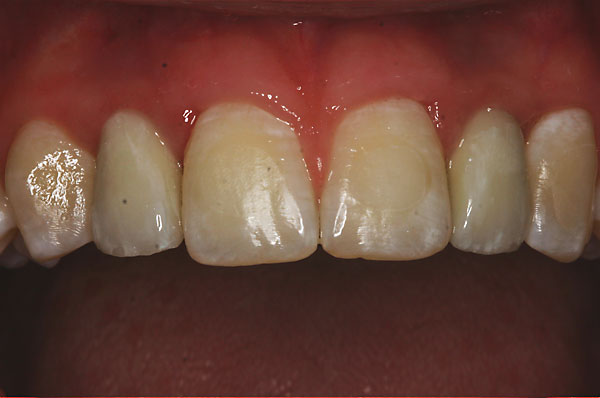

Fall: Einzelzahnlücke nach Zahnextraktion

![]() |